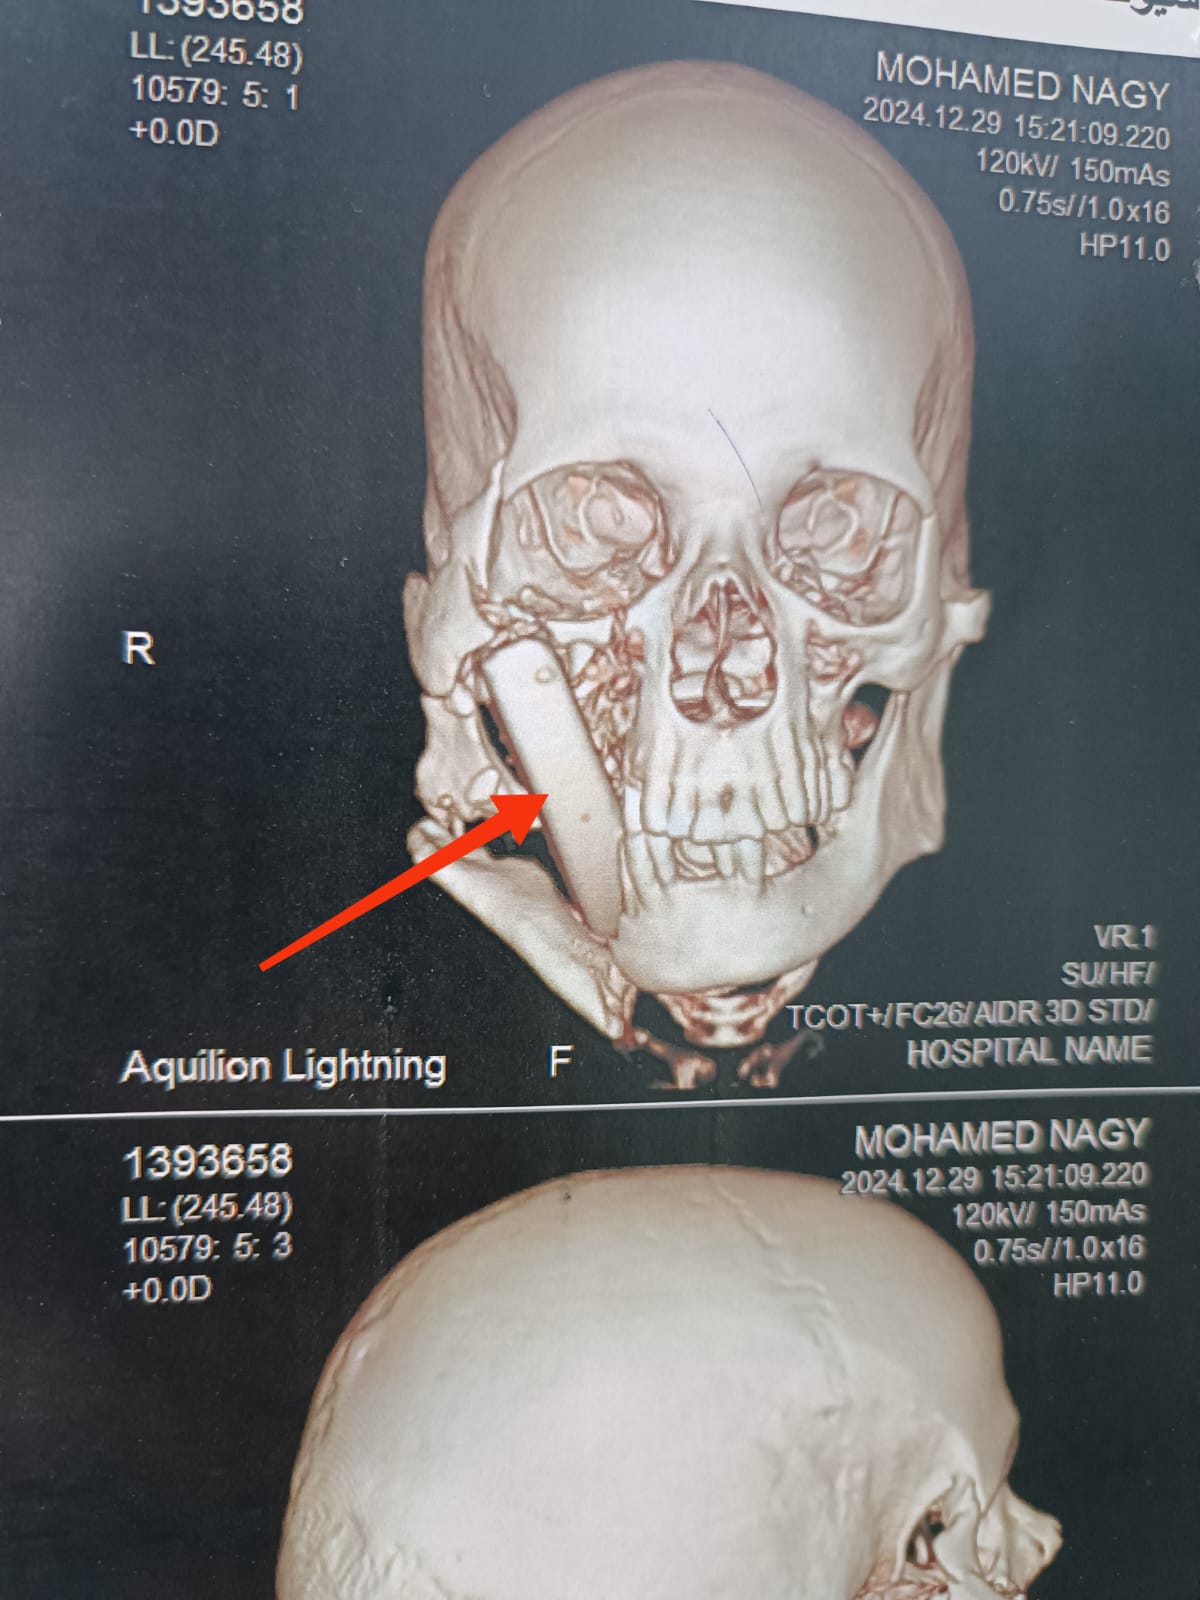

وكان مستشفي الإصابات الجامعي الجديد؛ استقبل مريضاً يبلغ من العمر ٥٠ عاماً، بعد تعرضه لإصابة بالغة أثناء أداء عمله بإحدى المناطق الحجرية، والذي نتج عنه تطاير قطعة حجرية كبيرة ارتطمت بوجه المصاب، وتسببت في حدوث تهتك بأنسجة الشفاه العلوية، واستقرت داخل أنسجة الخد الأيمن، مسببةً جروح بالغة؛ بالخد الأيمن، وقناة الغدة النكافية اليمنى، وسقف الحلق والبلعوم، كما تسبب فى كسور متعددة بعظام الوجنة اليمنى، والفك السفلى.

وتمكّن الفريق الطبي، بوحدة جراحات الوجه والفكين والرقبة؛ من تحضير المريض، والتدخل السريع؛ لإجراء جراحة عاجلة بعد عمل التجهيزات اللازمة، والإسعافات الأولية، ونجح الفريق في إصلاح أنسجة الخد، والفم، والبلعوم، مع استقرار الحالة الصحية للمريض بشكل جيد جداً، ويتم تجهيز المريض لمرحلة جراحية لاحقة؛ لتثبيت كسور الوجه.